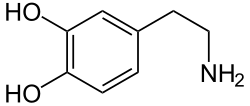

Dopamine system

The dopamine or dopaminergic system consists of several pathways, originating from the ventral tegmentum or substantia nigra as examples. It acts on dopamine receptors.[14]

Parkinson's disease is at least in part related to dropping out of dopaminergic cells in deep-brain nuclei, primarily the melanin-pigmented neurons in the substantia nigra but secondarily the noradrenergic neurons of the locus coeruleus. Treatments potentiating the effect of dopamine precursors have been proposed and effected, with moderate success.

Dopamine pharmacology

- Cocaine, for example, blocks the reuptake of dopamine, leaving these neurotransmitters in the synaptic gap for longer.

- AMPT prevents the conversion of tyrosine to L-DOPA, the precursor to dopamine; reserpine prevents dopamine storage within vesicles; and deprenyl inhibits monoamine oxidase (MAO)-B and thus increases dopamine levels.